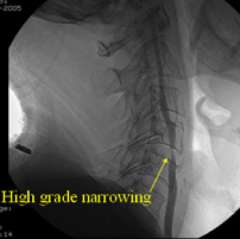

This is commonly referred to as "hardening of the arteries". It is actually a complex process of deposition of cholesterol and inflammation that leads to narrowing of a blood vessel (Figure 1) and/or a predisposition to blood clot formation. The main risk factors for development of atherosclerosis are elevated cholesterol, high blood pressure, smoking, diabetes, and genetics. This can occur anywhere in the body's blood vessels. It commonly occurs in the main arteries of the neck going to the brain (as shown in figure 1), which are called the carotid arteries. It can also occur in the blood vessels of the brain itself, and then it is called intracranial atherosclerosis. In both locations, strokes and TIAs can occur.